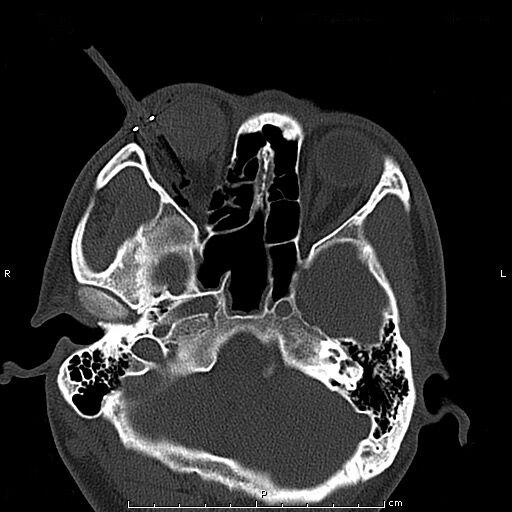

患者青年男性,因“右眼被鋼筆戳傷2小時余”入院,眼科查體:視力:右無光感,左0.4。眼壓:右不能檢查,左正常。右眼上瞼紅腫,鋼筆自顳上方眼瞼刺入,末端位置不詳,睜眼困難;結(jié)膜充血、水腫,角膜尚清,前房積血,余眼內(nèi)結(jié)構(gòu)窺不入。左眼未見明顯異常。入院后完善眼眶CT檢查,印象:右眼眶異物并右眼球破裂傷、眶內(nèi)壁骨折,異物嵌頓于眶壁。鋼筆內(nèi)含墨水,傷情重且復(fù)雜。

經(jīng)科室討論、充分評估患者病情,與患者進(jìn)行病情溝通后,擬于全麻下實施右眼眶壁異物取出+眼球破裂傷清創(chuàng)縫合探查+眼瞼皮膚裂傷清創(chuàng)縫合+萬古霉素玻璃體腔注藥術(shù)。由于鋼筆筆尖與筆筒游離且筆尖彎曲倒鉤于眶壁,使異物取出難度大大增加,經(jīng)專家團(tuán)隊討論,決定在鼻內(nèi)窺鏡協(xié)助下聯(lián)合眶內(nèi)入路分離、截斷內(nèi)直肌、下直肌成功將眶內(nèi)壁異物自鼻腔完整取出,手術(shù)取得圓滿成功。